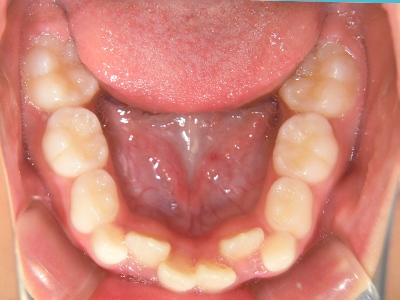

歯並びの相談に来られるお子様は、口呼吸をしているケースが多く、これが歯並びに大きな影響を与えています。

- 口呼吸をしている

↓ - 舌の位置が悪くなる

↓ - 頬の圧力が上の歯列にかかりやすくなる

↓ - 上あごが狭くなる

↓ - 下あごが狭くなる・下あごの位置が悪くなる

↓ - さまざまな不正咬合が生じる

ないき歯科クリニックでは、上あごの成長不足を補い、鼻呼吸を獲得しつつ歯列を整え、将来のお口をより健康な状態にすることをゴールに定める矯正治療をおこなっています。